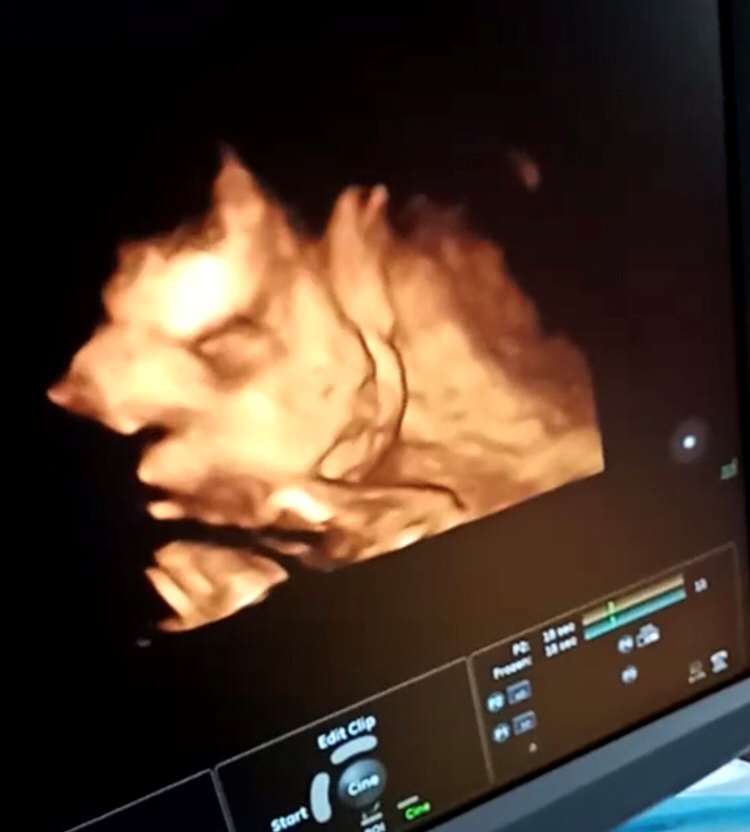

孕29周+6天

接健康女宝宝在我腹中,跪求女宝宝